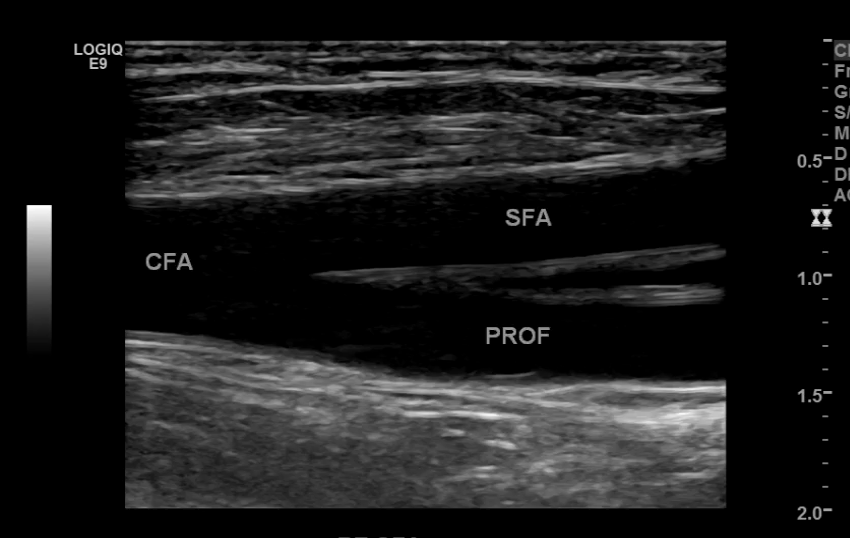

The iliac arteries bifurcate into external and internal iliac arteries (EIA and IIA). The EIA continues caudally turning into the common femoral artery (CFA) which further bifurcates into superficial femoral (SFA) and deep femoral artery (aka profunda femoris). The SFA then converts into the popliteal artery which bifurcates into the tibioperoneal trunk and anterior tibial artery (ATA). The tibioperoneal trunk bifurcates into posterior tibial artery (PTA) and the peroneal artery. The anterior tibial artery descends further to become the dorsalis pedis artery (DPA).

Common Femoral Artery

CFA and its branches